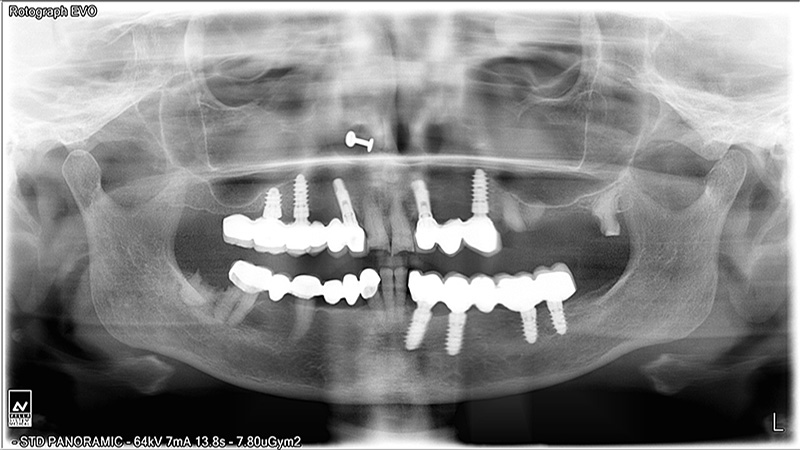

Implants

Implant Patients